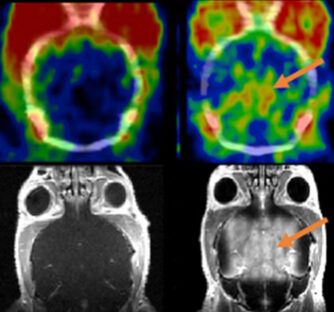

Monitoring connexin43 activity in the rodent brain using advanced MRI